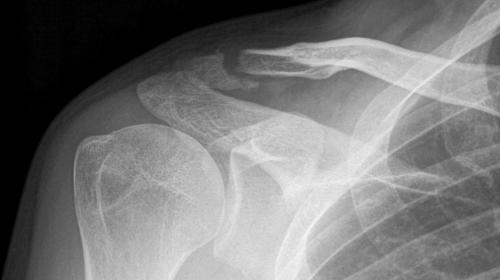

Es passierte am 21.09.2021 während einem Bahnrennen in Oerlikon. Im Rennen stürzte ich unglücklich und fiel ziemlich heftig auf die harte Betonbahn...

Die Diagnose kurz später im Spital:

Fraktur des linken Schlüsselbeins und des rechten Daumens.